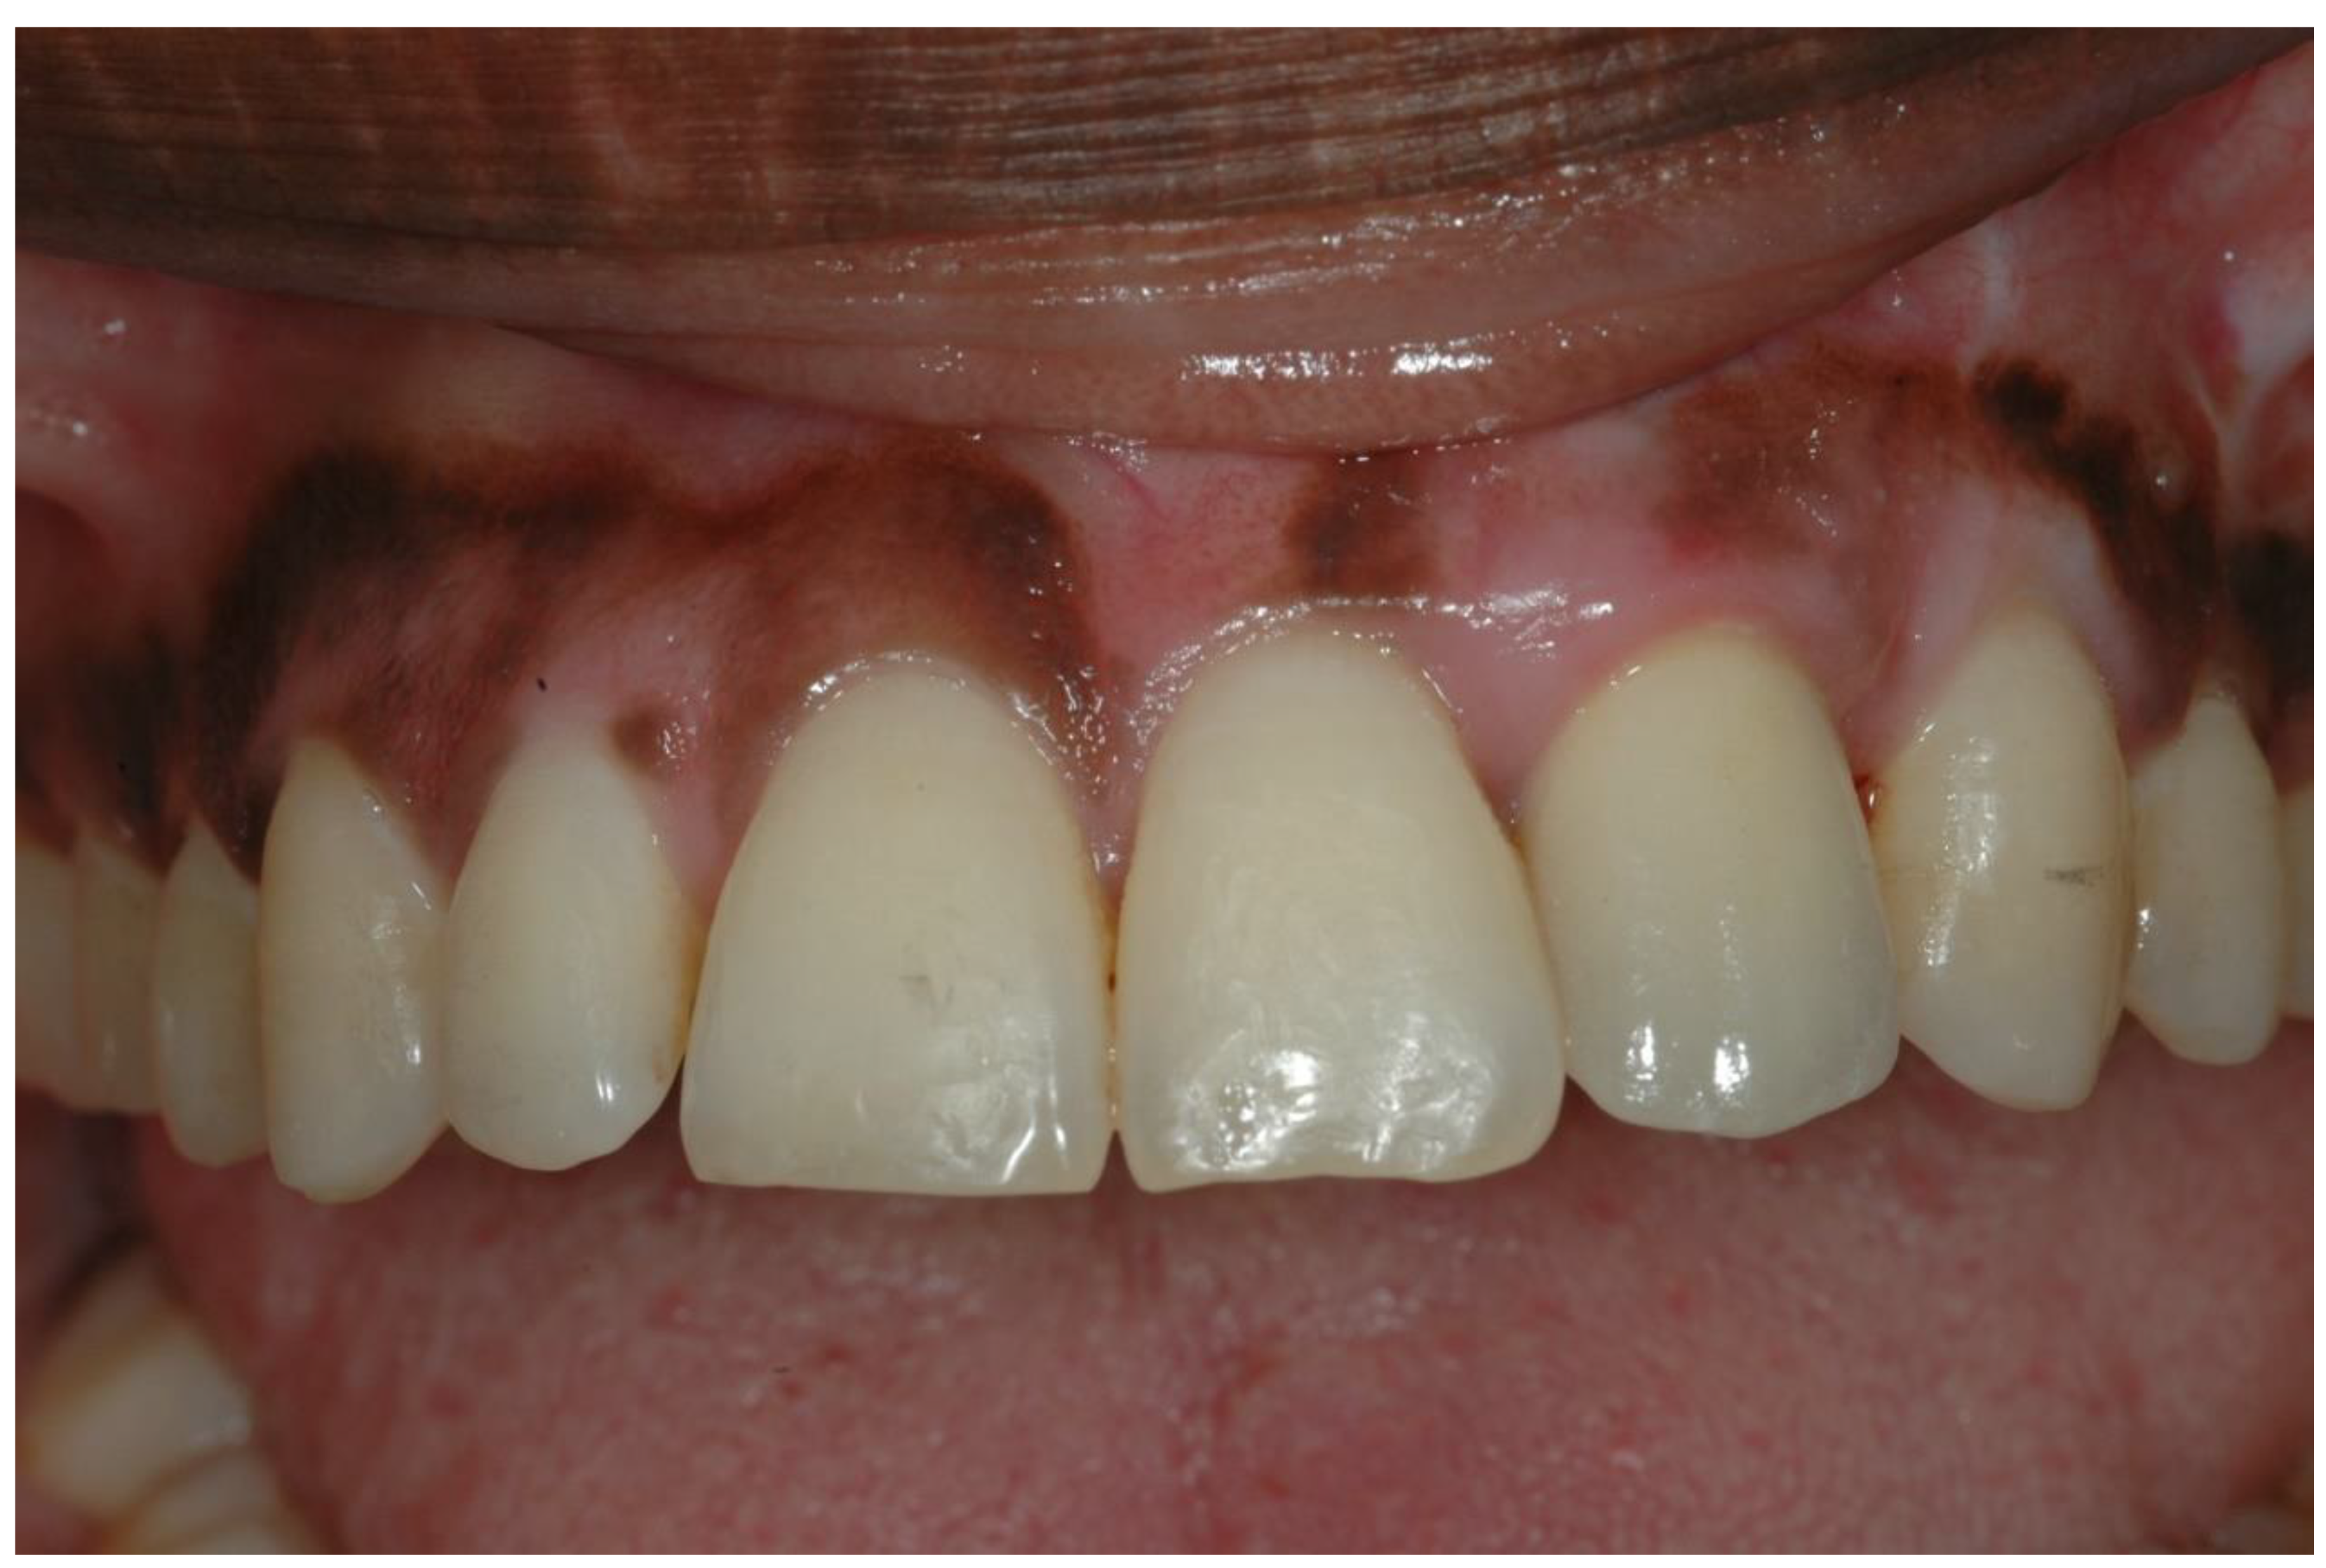

- Six months later, implant insertion followed immediately by a temporary restoration placement.

- Similar permanent ISP metal-free porcelain crown type performed in the same laboratory.